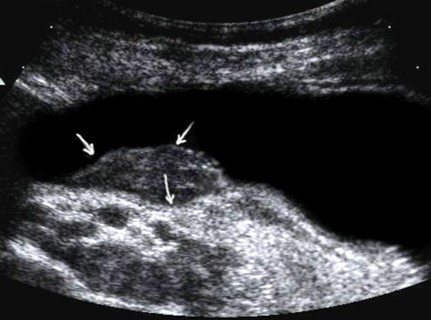

The polypoid type of gastric cancer was observed in 3 (4,9±2,8%) cases, the ulcerative type – in 18 (29,5±5,8%), the infiltrative ulcerative type – in 27 (44,3±6,4%) and the diffuse infiltrative type – in 13 (21,3%±5,2%) cases respectively (Table 2). On the echogram, the tumor was

Visualized as a polypoid formation on a wide base above the gastric mucosa of a non-uniform structure, an irregular surface (Figure 5, Figure 6, Figure 7).

Figure 5.The polypoid type of gastric carcinomas for T3 stage. On the posterior wall of the antrum, a polypoid formation with a fuzzy contour is visualized, the image of the mucous and serous membranes (arrows) is discontinuous.

Figure 6.The gastric carcinoma for T3 stage. The tumor is visualized as a polypoid formation on a wide base above the gastric mucosa of a non-uniform structure, an irregular surface (arrows).